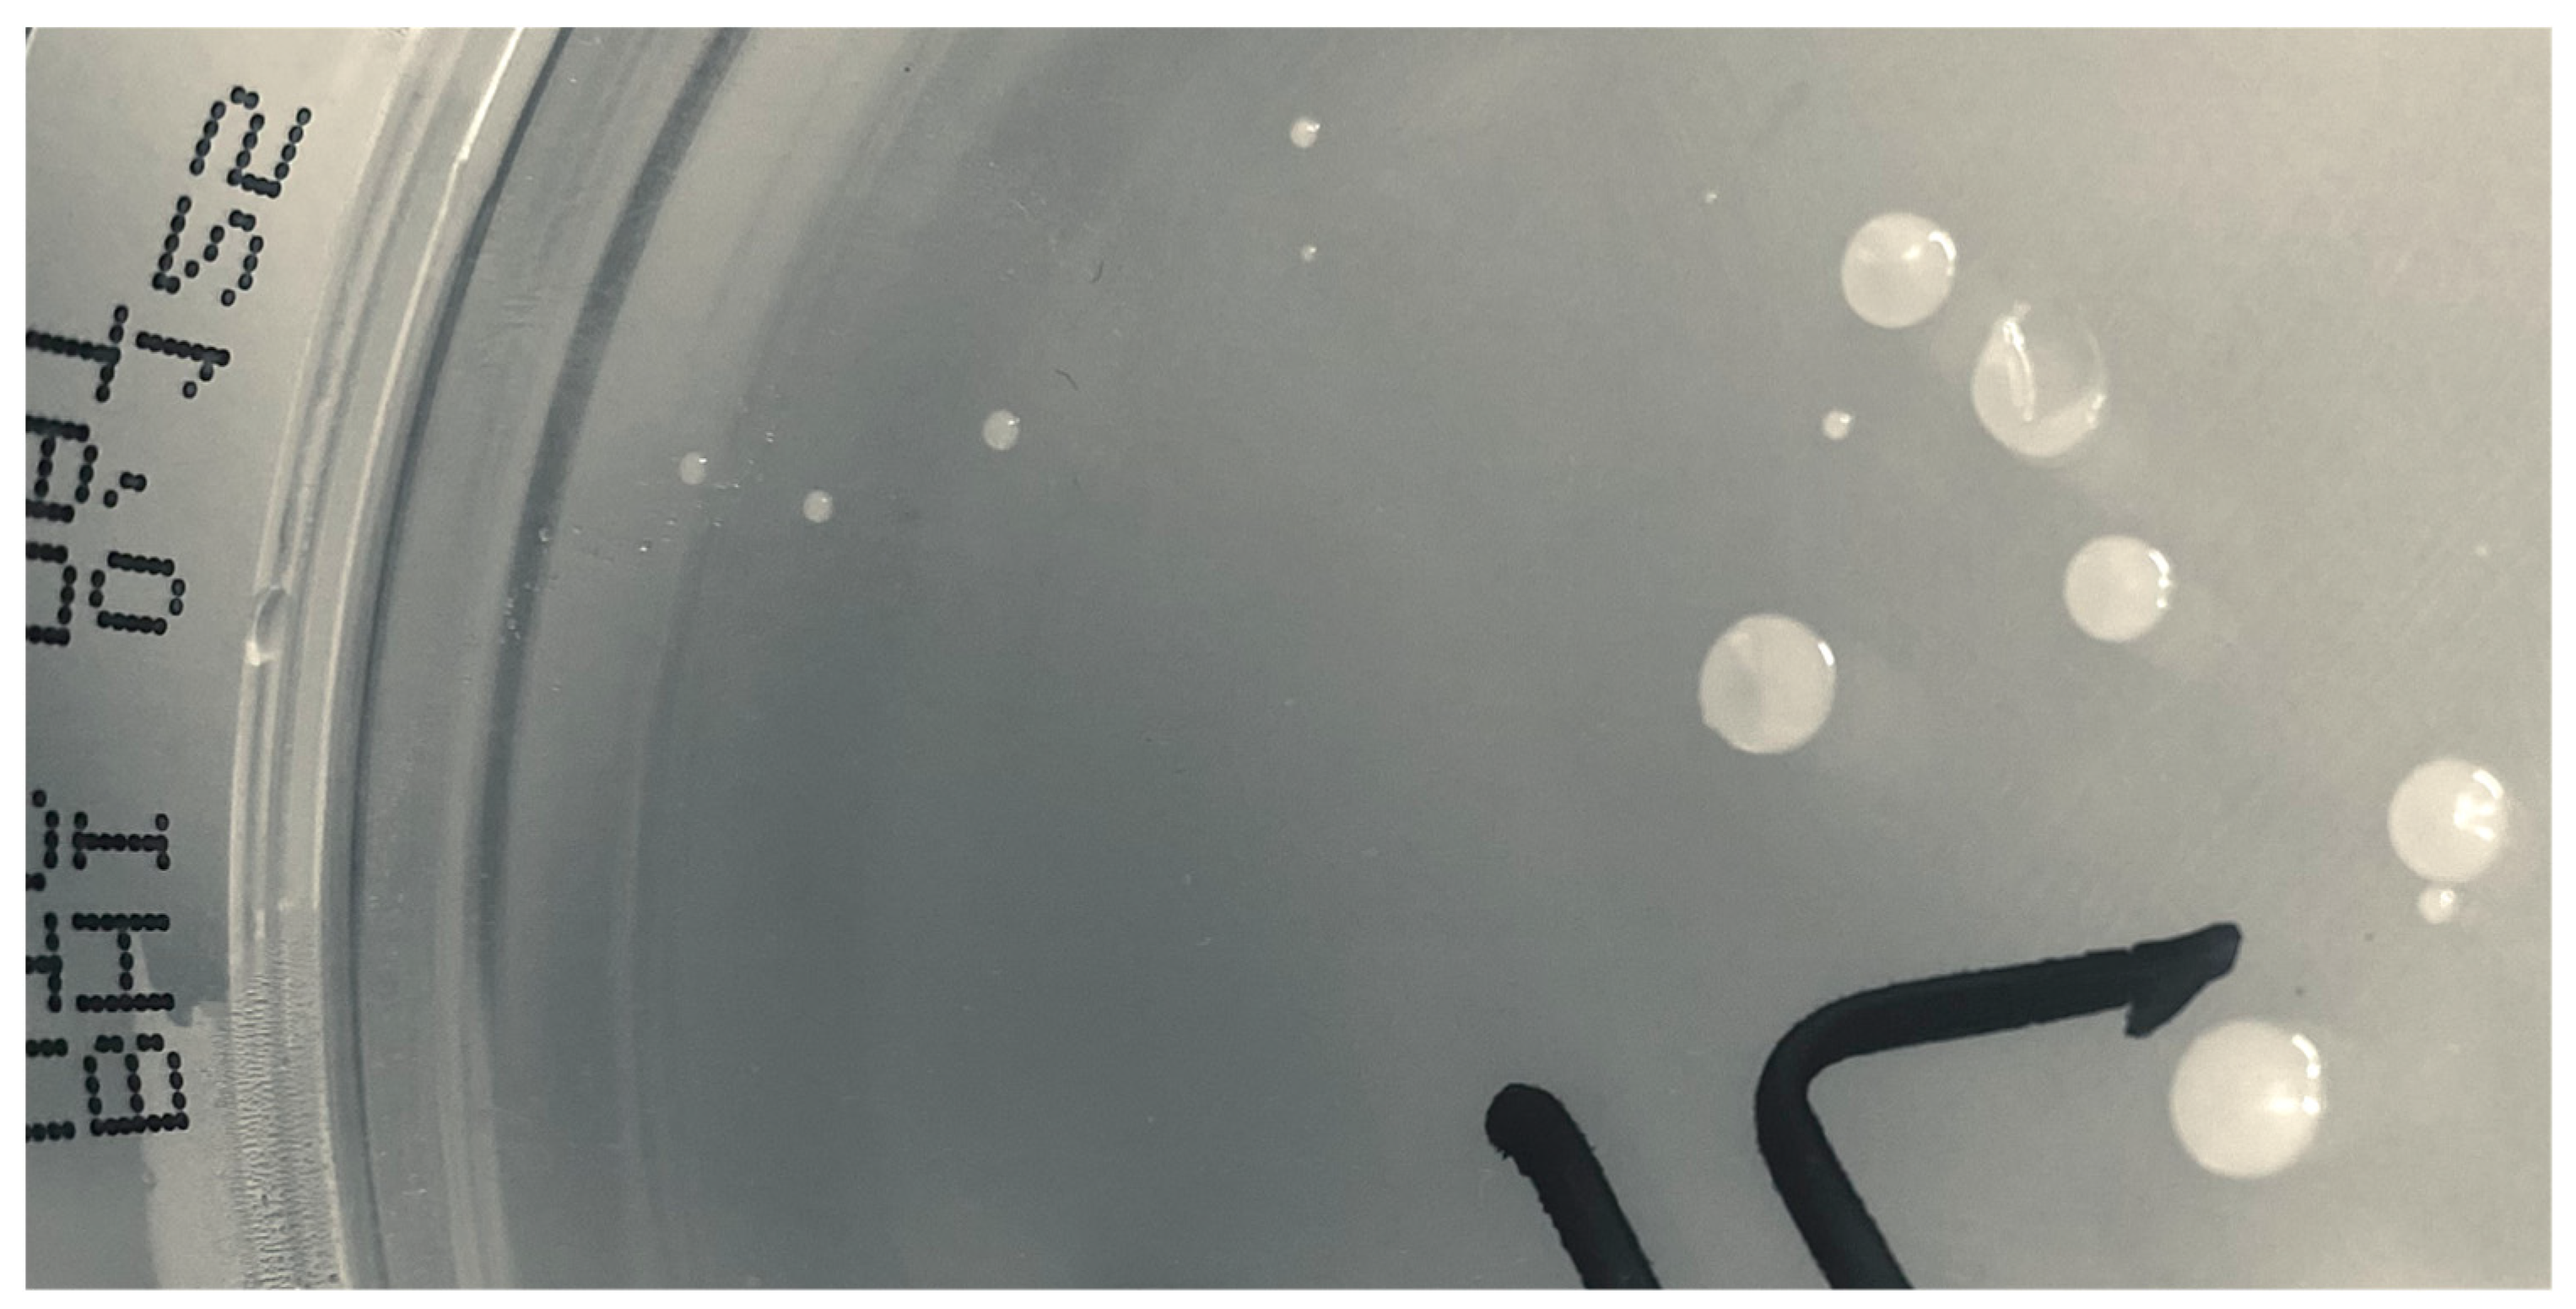

2.1. Bacterial Cultures